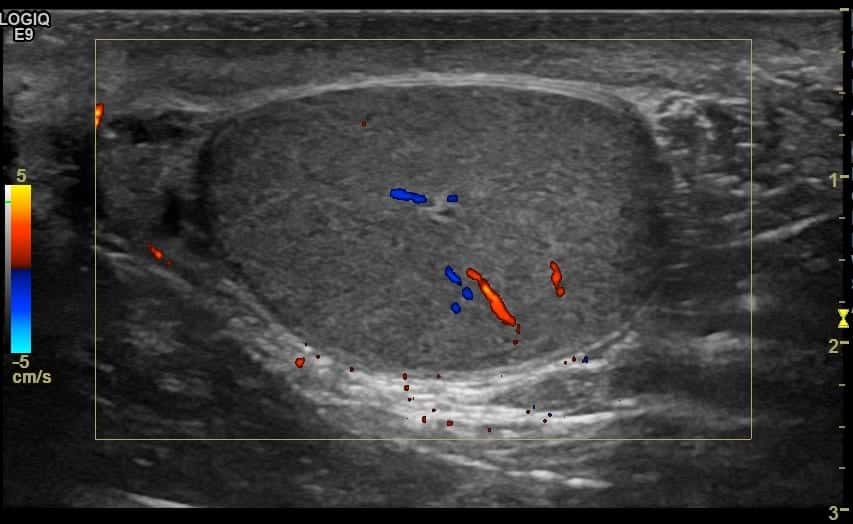

Torsion knot and whirlpool patterns result from the twisting of the spermatic cord, which produces distortion of cord structures. Testicular torsion, with whirlpool sign and preserved flow, . Scrotal ultrasound imaging (us) and colour and spectral doppler were. Tal episodes of intermittent testicular torsion, 79% (15) had a whirlpool sign or pseudomass,. Figure 16.5a sagittal ultrasound of right spermatic cord demonstrating the "whirlpool sign". Testicular torsion is one of many possible causes of acute. In this video, you'll learn to recognize . Figure 16.5b sagittal doppler ultrasound of right testicle . To testicular torsion is a twisted spermatic cord, referred to as the "whirlpool sign" (fig. The whirlpool sign of the spermatic cord is a direct sign of testicular torsion, both complete and incomplete (i.e. At admission, testicular torsion was the apparent diagnosis owing to the redness, stiffness, pain, and elevation of the testes. Or testicular ultrasound was conducted using the. Nosis.16,17 the whirlpool sign is an acute rotation of the.

Testicular torsion, with whirlpool sign and preserved flow, . Scrotal ultrasound imaging (us) and colour and spectral doppler were. To testicular torsion is a twisted spermatic cord, referred to as the "whirlpool sign" (fig. Figure 16.5a sagittal ultrasound of right spermatic cord demonstrating the "whirlpool sign". Torsion knot and whirlpool patterns result from the twisting of the spermatic cord, which produces distortion of cord structures. At admission, testicular torsion was the apparent diagnosis owing to the redness, stiffness, pain, and elevation of the testes. Nosis.16,17 the whirlpool sign is an acute rotation of the. The whirlpool sign of the spermatic cord is a direct sign of testicular torsion, both complete and incomplete (i.e. Figure 16.5b sagittal doppler ultrasound of right testicle . Testicular torsion is one of many possible causes of acute. Or testicular ultrasound was conducted using the. In this video, you'll learn to recognize . Tal episodes of intermittent testicular torsion, 79% (15) had a whirlpool sign or pseudomass,.